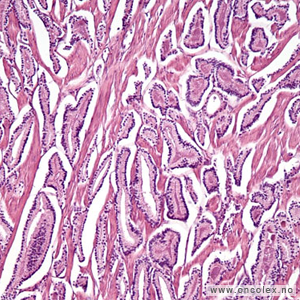

Analyse av vevsprøver

Vevsprøver sendes til histologisk analyse. Analysene kan være avgjørende for hvilken behandling pasienten får. Når patologen undersøker vevsprøvene i mikroskop blir det angitt hvor det er påvist kreft, hvor mange millimeter karsinom det er i hver vevsprøve i forhold til den totale mengde av vevsprøver. Det angis også om det er kribriform vekst, perinevral infiltrasjon og infiltrasjon i fettvev eller sædblærer (vesicula seminalis), hvis dette er kommet med i vevsprøvene. Vevsprøven typebestemmes og graderes (Gleason og/eller ISUP).

95 % av kreftsvulstene i prostata er adenokarsinomer som utgår fra kjertelendestykkene og gangene i prostata. De vokser multifokalt i prostata og gir ofte ingen synlige tumorknuter i mikroskop. Vel 75% av tilfellene oppstår i bakre del av prostata.

De fleste kreftsvulster i prostata er av en acinær (bærformet) type og kalles ofte bare prostatakarsinom. Vel 1% av prostatakarsinomene utgjøres av andre varianter som ofte har dårlig prognose (duktalt karsinom, mucinøst karsinom, signetringcellekarsinom og småcellet karsinom). 5% av krefttilfellene i prostata utgjøres av andre typer som utgår fra overgangsepitelet i urinrøret/pars prostatica urethra (urothelialt karsinom), støttevevet (sarkomer) eller lymfoid vev (lymfomer).

Bildeeksempler av vevsprøver

Gleasongraderinger

Ved prostatakreft anvendes et særskilt graderingssystem som ble beskrevet av patologen Donald Gleason i 1966. Dette samsvarer sterkt til prognosen. I motsetning til WHO baserer Gleasongradering/Gleason score (GS) seg kun på kjertlenes arkitektur og cellenes sammensetning, ikke cellenes atypi. De senere årene har ISUP gradering kommet i bruk, det er forsåvidt en forenkling av GS med et tall fra 1-5 hvor ISUP 1 = GS6, ISUP 2 = GS 7a, ISUP 3 = GS7b, ISUP 4 = GS8 og ISUP 5 = GS 9 og 10.

De mest aggressive svulstene har Gleasongrad 5, score 9–10 = ISUP 5. Gleason score (GS) angis for hver nålebiopsi som summen av den dominerende og sekundære grad. Den sekundære grad oppgis bare dersom den utgjør mer enn 5%.

Tertiær Gleasongrad 4 eller 5 rapporteres selv om de utgjør < 5%. Ved Gleasonscore 7b (4+3) er den dominerende Gleasongrad 4. Disse har dårligere prognose enn Gleasonscore 7a. Svulster med Gleasonscore 6 er lavgradig, Gleasonscore 7 er intermediære, mens Gleasonscore 8–10 er høygradige.